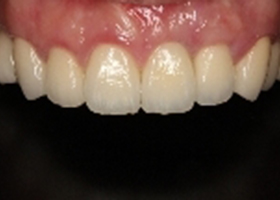

病患治療後,最終假牙完成照。

proimages/case/cosmetic/pic_case-084.jpg